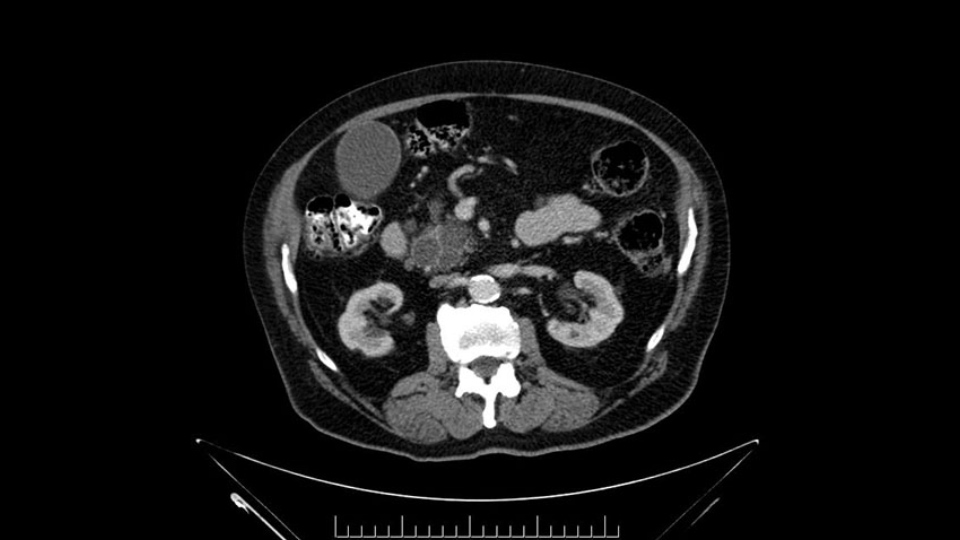

The next item that I would look at: the issue would be the vessels and usually start at the portal vein, watch the portal vein, follow it down, down-down-down to the neck of the pancreas - which is here - and there’s no impingement by tumor, which is great. The SMV and the splenic vein, which is here. The splenic vein junction is normal, which is great.

Then look at the first jejunal branch - which is this thing here - this little branch which goes under the SMA. It’s something that we’ve just started appreciating over the past few years and the reason for that is: there’s two or three small branches that come out of the uncinate into the the first jejunal and it’s a fairly inevitable part of the operation where there’s some bleeding. As long as you’re cognizant of what’s happening, it’s no reason to panic and that kind of bleeding will eventually stop or can be stopped but it’s not easy because these little vessels are fragile from the uncinate to the first jejunal. So I do focus on that and it’s pretty consistent I’d say 9 times out of 10, people have that first jejunal.

In planning for my further steps, the first key that I find, first do a gentle mobilization of the hepatic flexure of colon completely away because that’s going to help me do a good wide Kocher maneuver. Why do I slow down? Because there are small tributaries and small blood vessels which communicate between the transverse mesocolon and the head of the pancreas and you also have the loop of Henle all the blood vessels which drain into the superior mesenteric vein just as it gets underneath the neck of the pancreas.

The initial hepatic flexure mobilization and the Kocher procedure is then going to enable me to understand the uncinate process of this patient, which should not be a problem, again. But the initial pictures had shown a degree of touching. I would not even say involvement or abutment; a degree of touching with the superior mesenteric vein. So that would give me an early chance to assess how the superior mesenteric vein is in this patient. So this would be the initial slowing down moment.

The first steps of a pancreaticoduodenectomy involve ensuring the CT findings are correct: exploring for signs of metastatic disease, peritoneal implants involving the omentum or the undersurface of the diaphragm and if again this is confirmed exploration that there's no metastatic disease, I begin the mobilization and really determining the relationship of the tumor with the major visceral vessels. I start by an extended Kocher maneuver, identify the superior mesenteric vein below the neck of the pancreas. They’re very thin walled vessels and as you're dissecting you have to use the ultimate care and meticulously dissect the superior mesenteric vein, ligate the anterior branches and begin the dissection from below to under the neck of the pancreas. At this point, if there's no reason to be concerned about whether there is any vascular invasion below, I usually take the gallbladder down. I mobilize the common hepatic duct above the insertion of the gallbladder. This patients already has a stent in place. So I would divide the bile duct at this point. This facilitates the dissection of the anterior surface of the portal vein and as I would expect looking at this imaging that there is nothing to be concerned about in terms of vascular involvement.